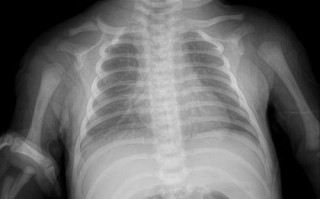

新生儿拍X光片到底会不会对身体造成潜在影响?

这是一个非常重要且常见的问题,新手父母们对此非常关心,在医生认为必要的情况下,给新生儿拍片子(医学影像检查)的益处远大于其潜在的风险,下面我将从几个方面为您详细解释,帮助您全面了解这个问题,为什么新生...

新生儿接受X光检查会有哪些潜在影响与风险?

在现代医学规范下,对新生儿进行必要的X光检查,其带来的诊断益处远远大于其潜在的风险, 医生只有在权衡利弊,认为检查对诊断和治疗至关重要时,才会开具X光检查,下面我们来分解说明:X光对新生儿的主要潜在风...